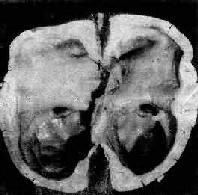

脑积水

图16-9 脑积水

侧脑室高度扩张,脑组织受压萎缩变薄